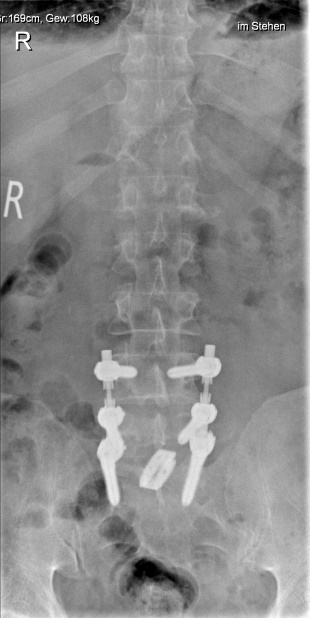

Der Begriff Osteochondrose beinhaltet den Verschleiß eines oder mehrerer Bewegungssegmente der Wirbelsäule. Häufigste Lokalisation ist der Zwischenwirbelraum der unteren Lendenwirbelsäule. Dabei kann es durch den Verschleiß der Bandscheibe zur lokalen Rücken/Nacken-Beschwerden kommen oder durch daraus resultierende Instabilität eine Spinal- oder Nerveneinengung mit ausstrahlenden Beschwerden verursachen. Im fortgeschrittenen Stadium kann dies auch zu ausgeprägten Wirbelsäulenverkrümmungen führen, die dann möglicherweise einen "Ganzwirbelsäulenschmerz" verursachen. Die Therapie der Wahl bei Osteochondrose an der Lendenwirbelsäule ist nach Ausschöpfung der konservativen Therapiemaßnahmen die Spondylodese oder Versteifung. Dabei werden nur die betroffenen Bereiche mit einem Schraubenstabsystem überbrückt und die verschlissenen Bandscheiben durch einen Platzhalter ersetzt.

Beispiel Osteochondrose